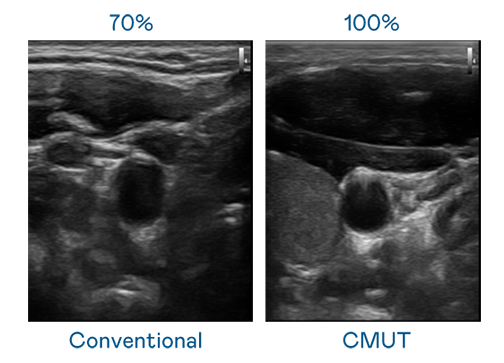

CMUT 技術是一種用電容式微機電元件來產生超音波訊號的技術。與傳統 PZT 壓電式技術相比,CMUT 頻寬增加 30%,更寬頻的超音波訊號讓影像解析度大幅提升,是實現高影像品質醫療超音波掃描、促進精準醫療發展的關鍵技術。

超音波影像的解析度高低,首先取決於探頭能發出的訊號頻寬。AG旗舰厅 CMUT 可提供高清晰的超音波訊號,提供高頻寬、高靈敏度、影像紋理細節更高的超音波影像,協助醫護人員縮短影像判讀時間及利用精準的醫療影像進行診斷。